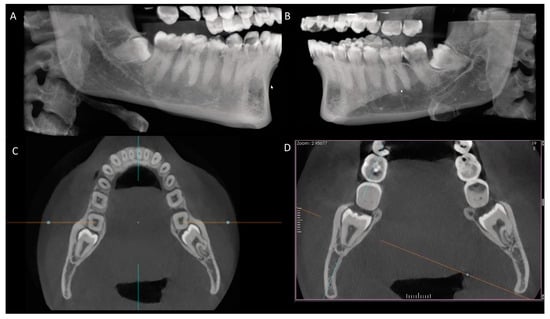

2. Materials and Methods

3.2. Positioning of Impacted Third Molars

3.3. Anatomical Relationship between the Root Apex of the Impacted Third Molar and the Mandibular Canal

3.4. Occurrence of External Root Resorption on the Distal Side of the Mandibular Second Molar